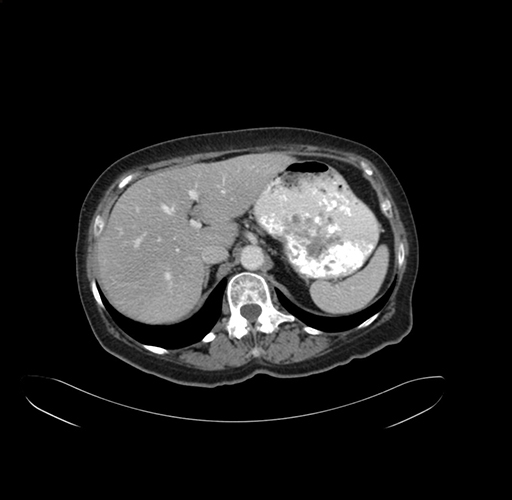

Pre-Chemo: Axial Venous